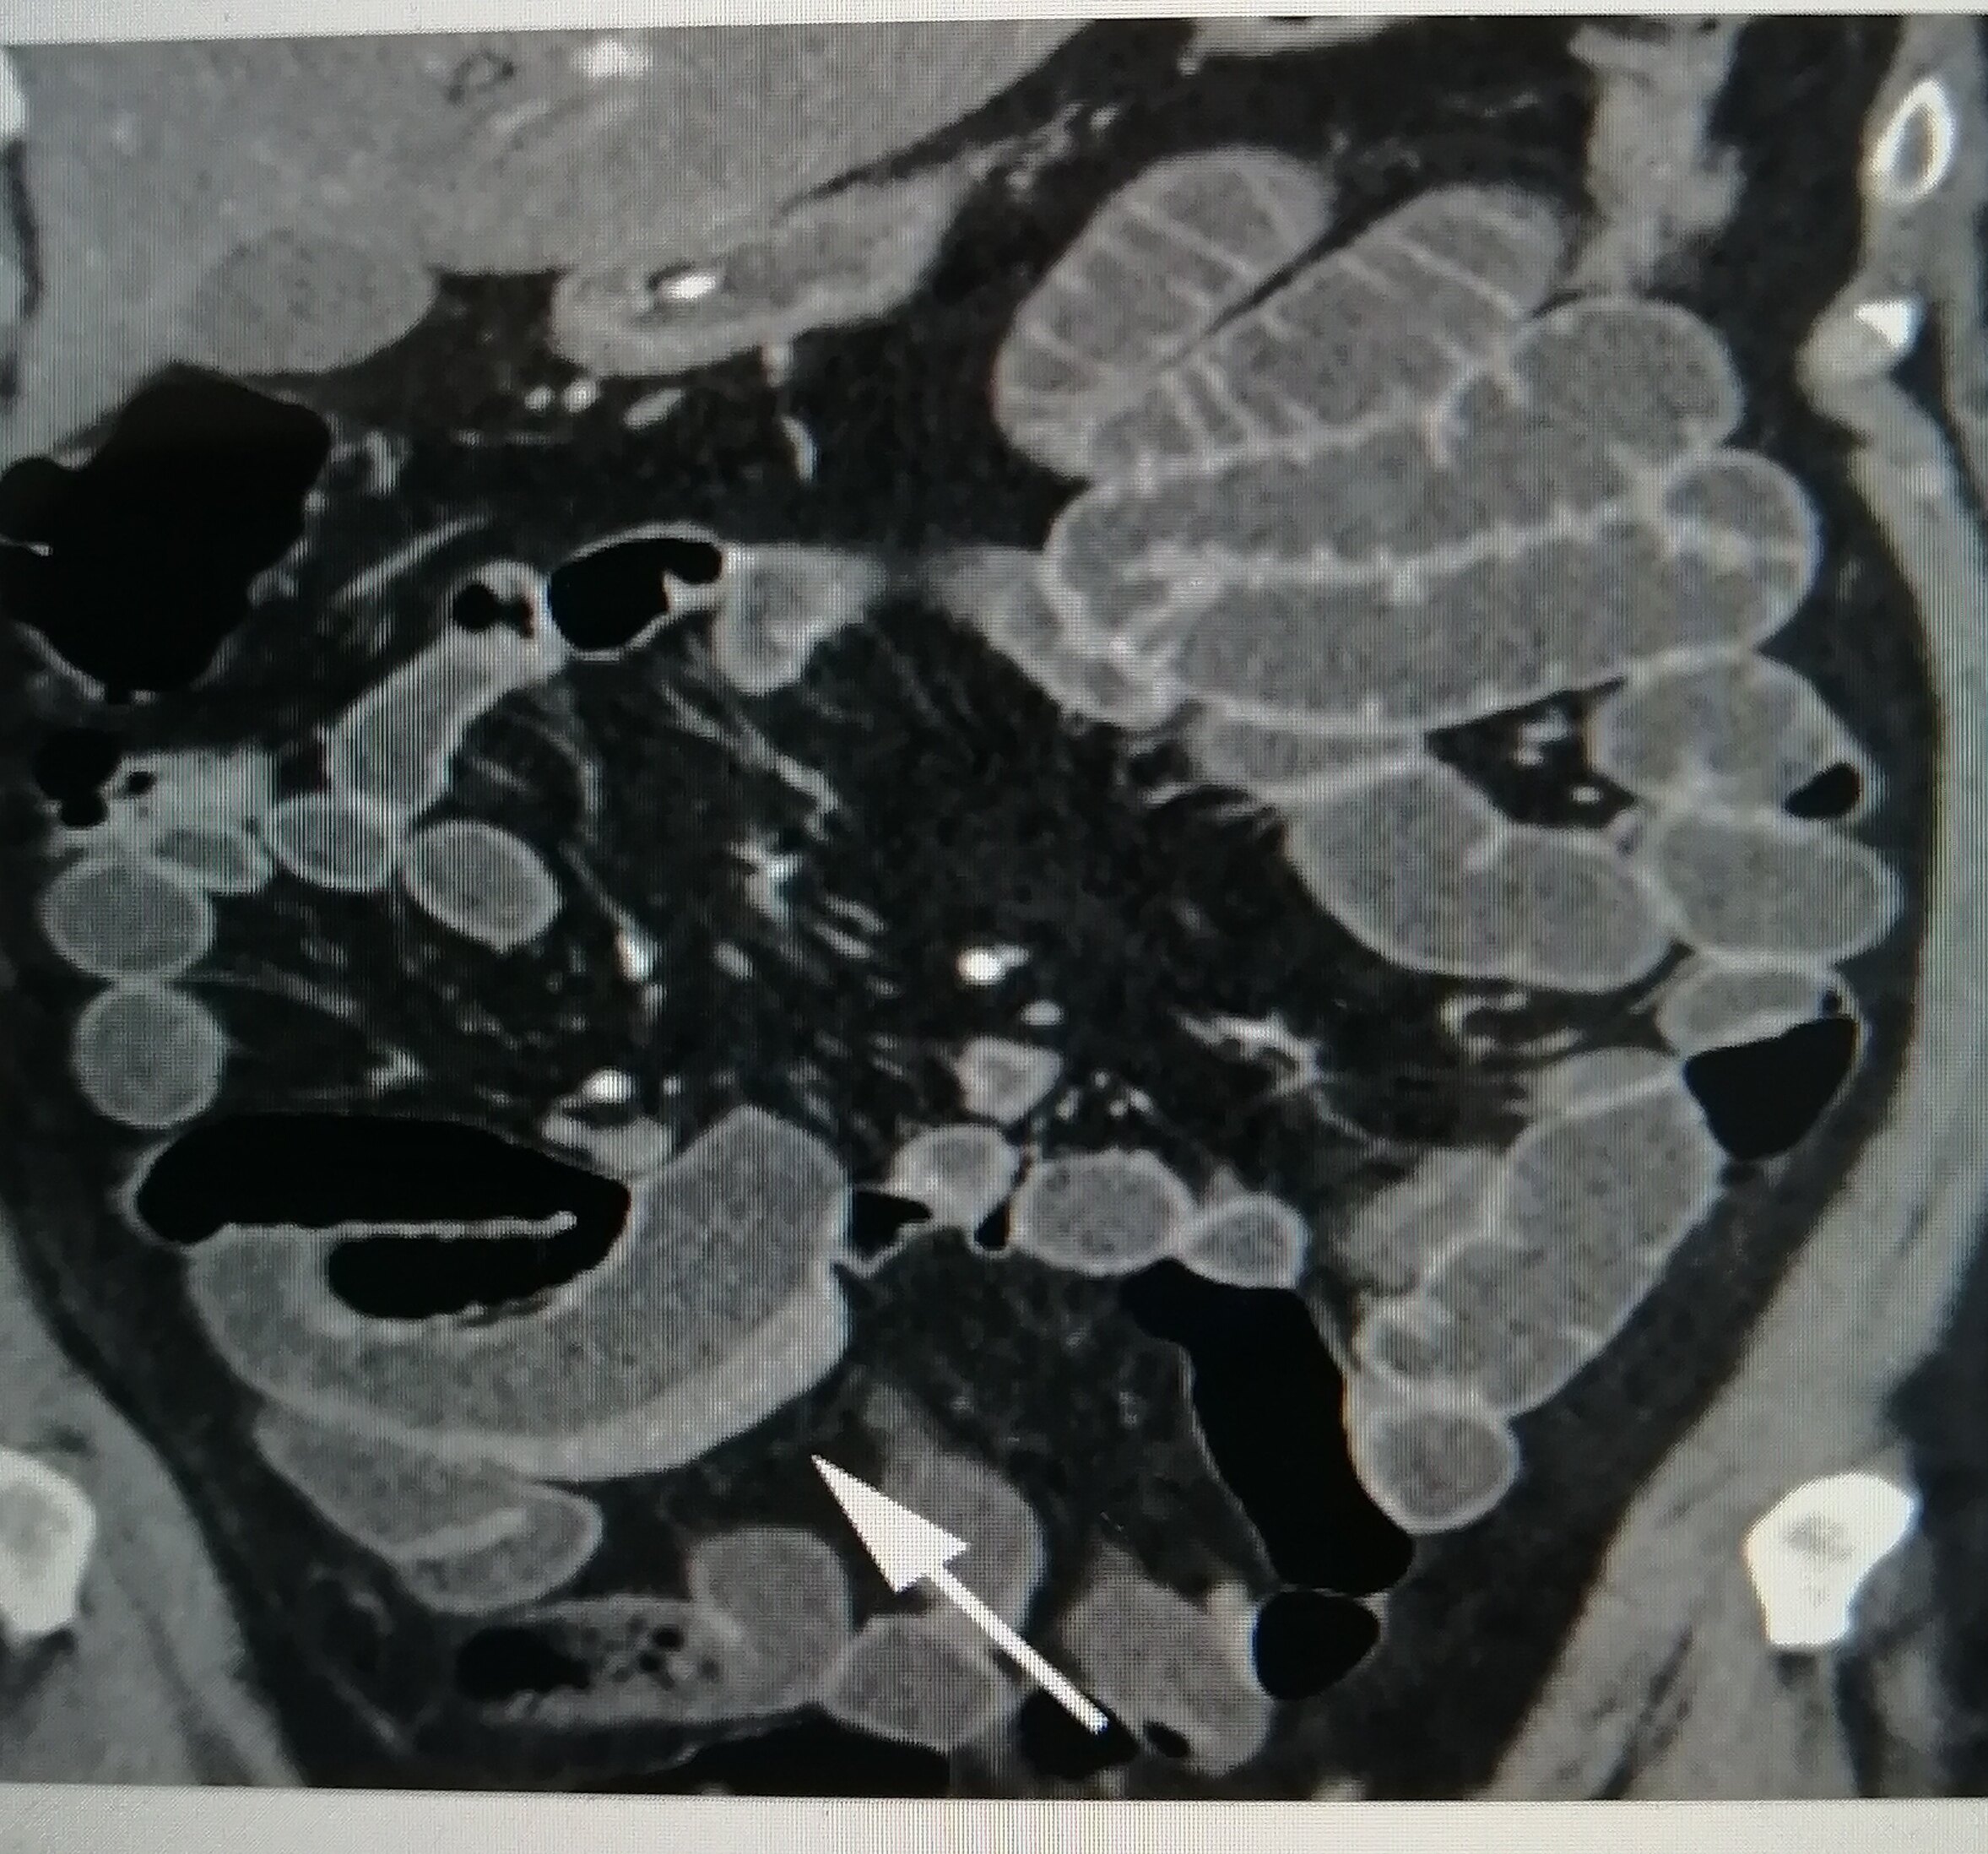

每当我想起那些在X光片上蜿蜒曲折的线条,我的心就忍不住揪成一团。克罗恩病,这个听起来既陌生又让人心生畏惧的名字,它的X线表现就像是命运在人体内肆意涂鸦的痕迹。

想象一下,那些线条如同顽皮的孩子,在肠道壁上留下不可磨灭的印记。它们或直或弯,或粗或细,每一道都像是诉说着一个不为人知的故事。有时候,它们聚集在一起,形成一个个小坑洼,仿佛是肠道在无声地哭泣,诉说着它们的疼痛和无奈。

更让人心痛的是,这些线条并不孤单,它们常常伴随着肠道的狭窄和瘘管的形成。这些变化,就像是一场场无情的战争,在人体内部悄然上演。每一次检查,都像是在揭开一层层伤疤,让人既期待又害怕。